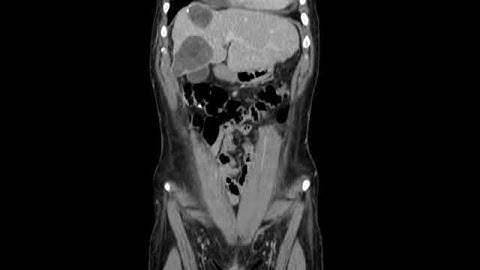

Laparoscopic left hepatectomy for hydatid cyst in close relation to MHV